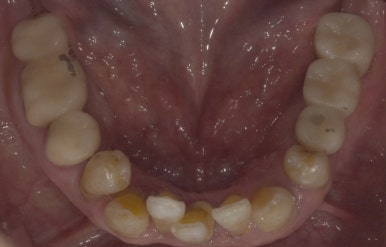

환자분의 첫 내원 시 엑스레이 사진과 입 안 사진을 함께 보여드리겠습니다.

임플란트 수술 전

2022-08-23

보시다시피 왼쪽 아래 어금니 3개를 상실한 상태에서 저희 치과로 내원해주셨는데요.

전후 사진을 보시면 텅 비어있던 왼쪽 아래부분이 임플란트 후 잘 채워져있는 것을 보실 수 있습니다.